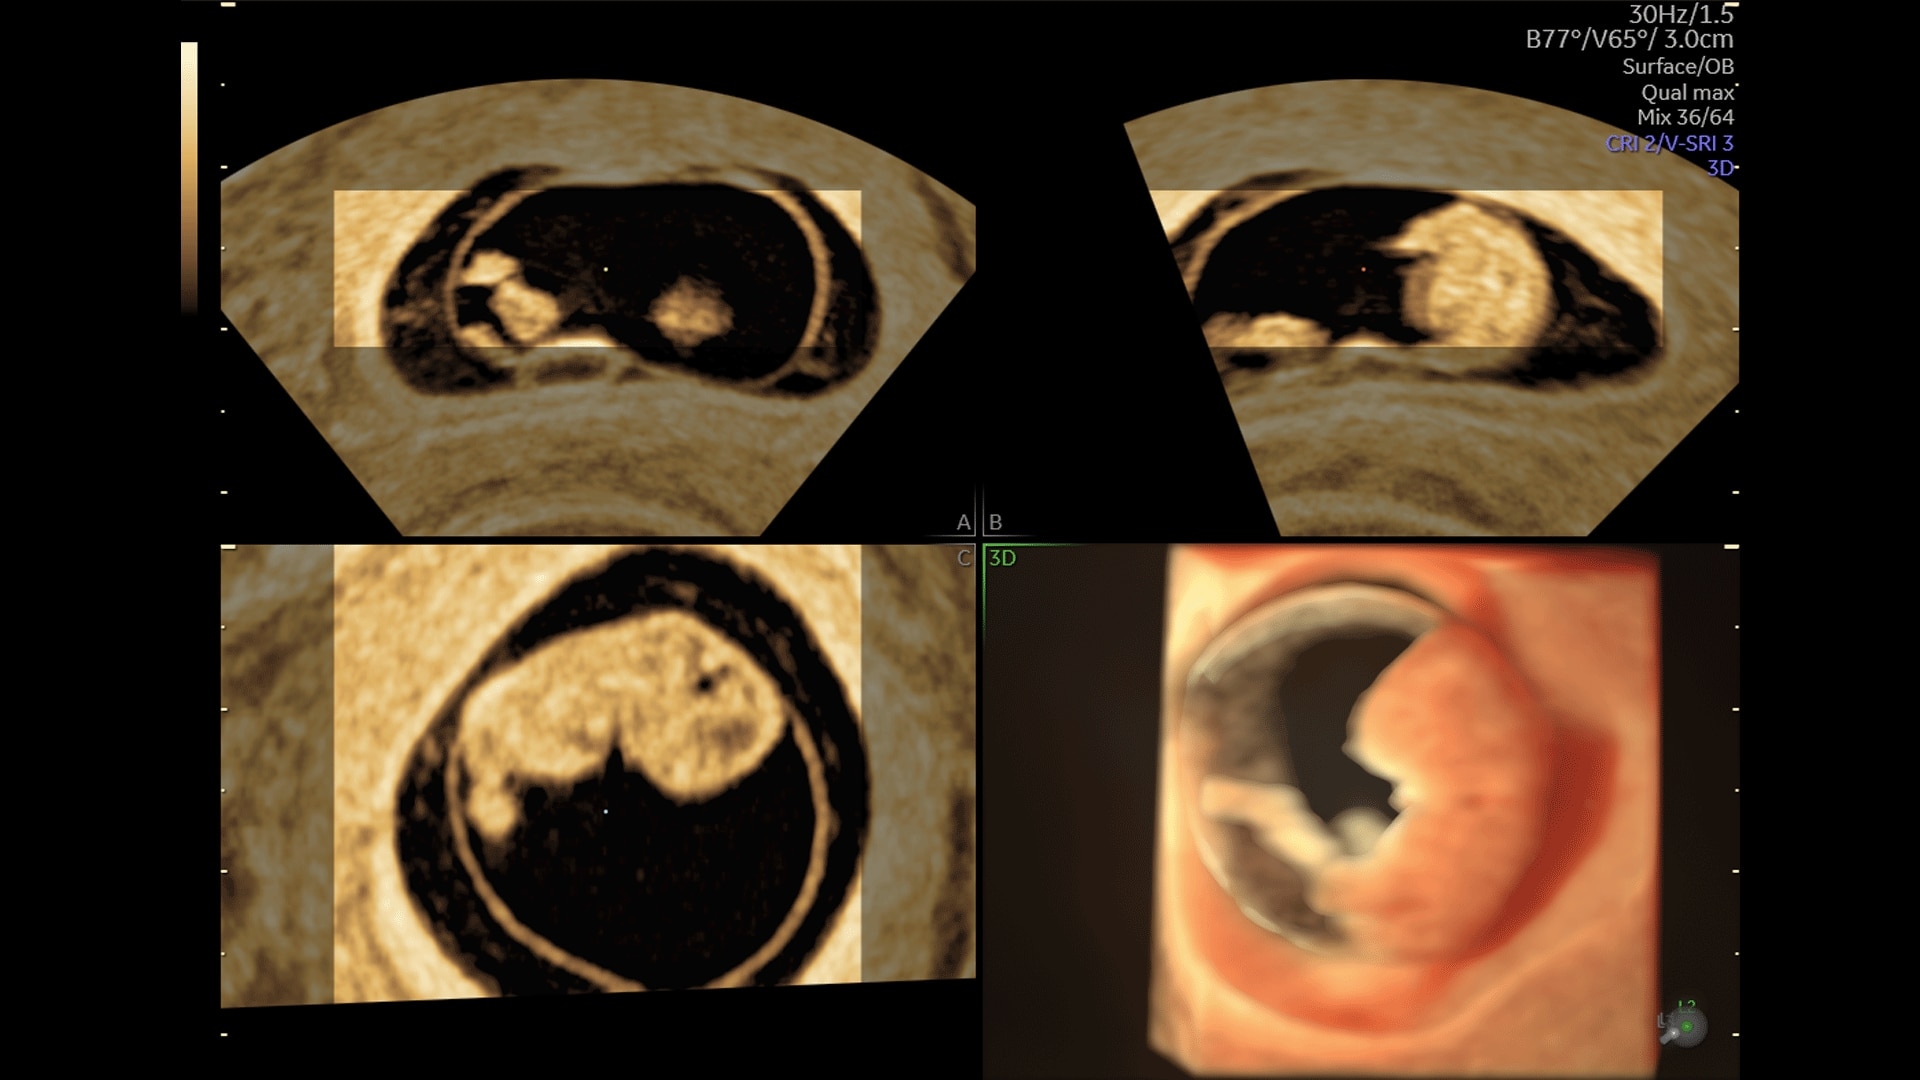

Extraordinary clarity and definition so you can focus on early detection and intervention.

Generate spectacular 2D/3D and color Doppler images with increased penetration and stunning clarity, to help visualize critical details needed for diagnostic assurance. The Lyric Architecture unlocks new imaging and processing power to expand your imaging capabilities for years to come